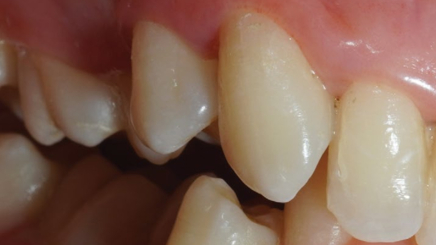

Хронический пародонтит средней степени тяжести

Результат через 2 недели

Вектор терапия по схеме, затем ФДТ 2-3 раза в неделю Сочетание периоскан, вектор-терапии и ФДТ 2-3 раза через неделю.

Гингивит и легкая степень пародонтита

Результат спустя неделю